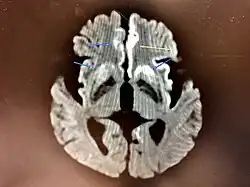

The classic histologic appearance is spongiform change in the gray matter: the presence of many round vacuoles from one to 50 micrometers in the neuropil, in all six cortical layers in the cerebral cortex, or with diffuse involvement of the cerebellar molecular layer.[59] These vacuoles appear glassy or eosinophilic and may coalesce. Neuronal loss and gliosis are also seen.[60] Plaques of amyloid-like material can be seen in the neocortex in some cases of CJD.[61]

However, extra-neuronal vacuolization can also be seen in other disease states. Diffuse cortical vacuolization occurs in Alzheimer's disease, and superficial cortical vacuolization occurs in ischemia and frontotemporal dementia. These vacuoles appear clear and punched out. Larger vacuoles encircling neurons, vessels, and glia are a possible processing artifact.[58]